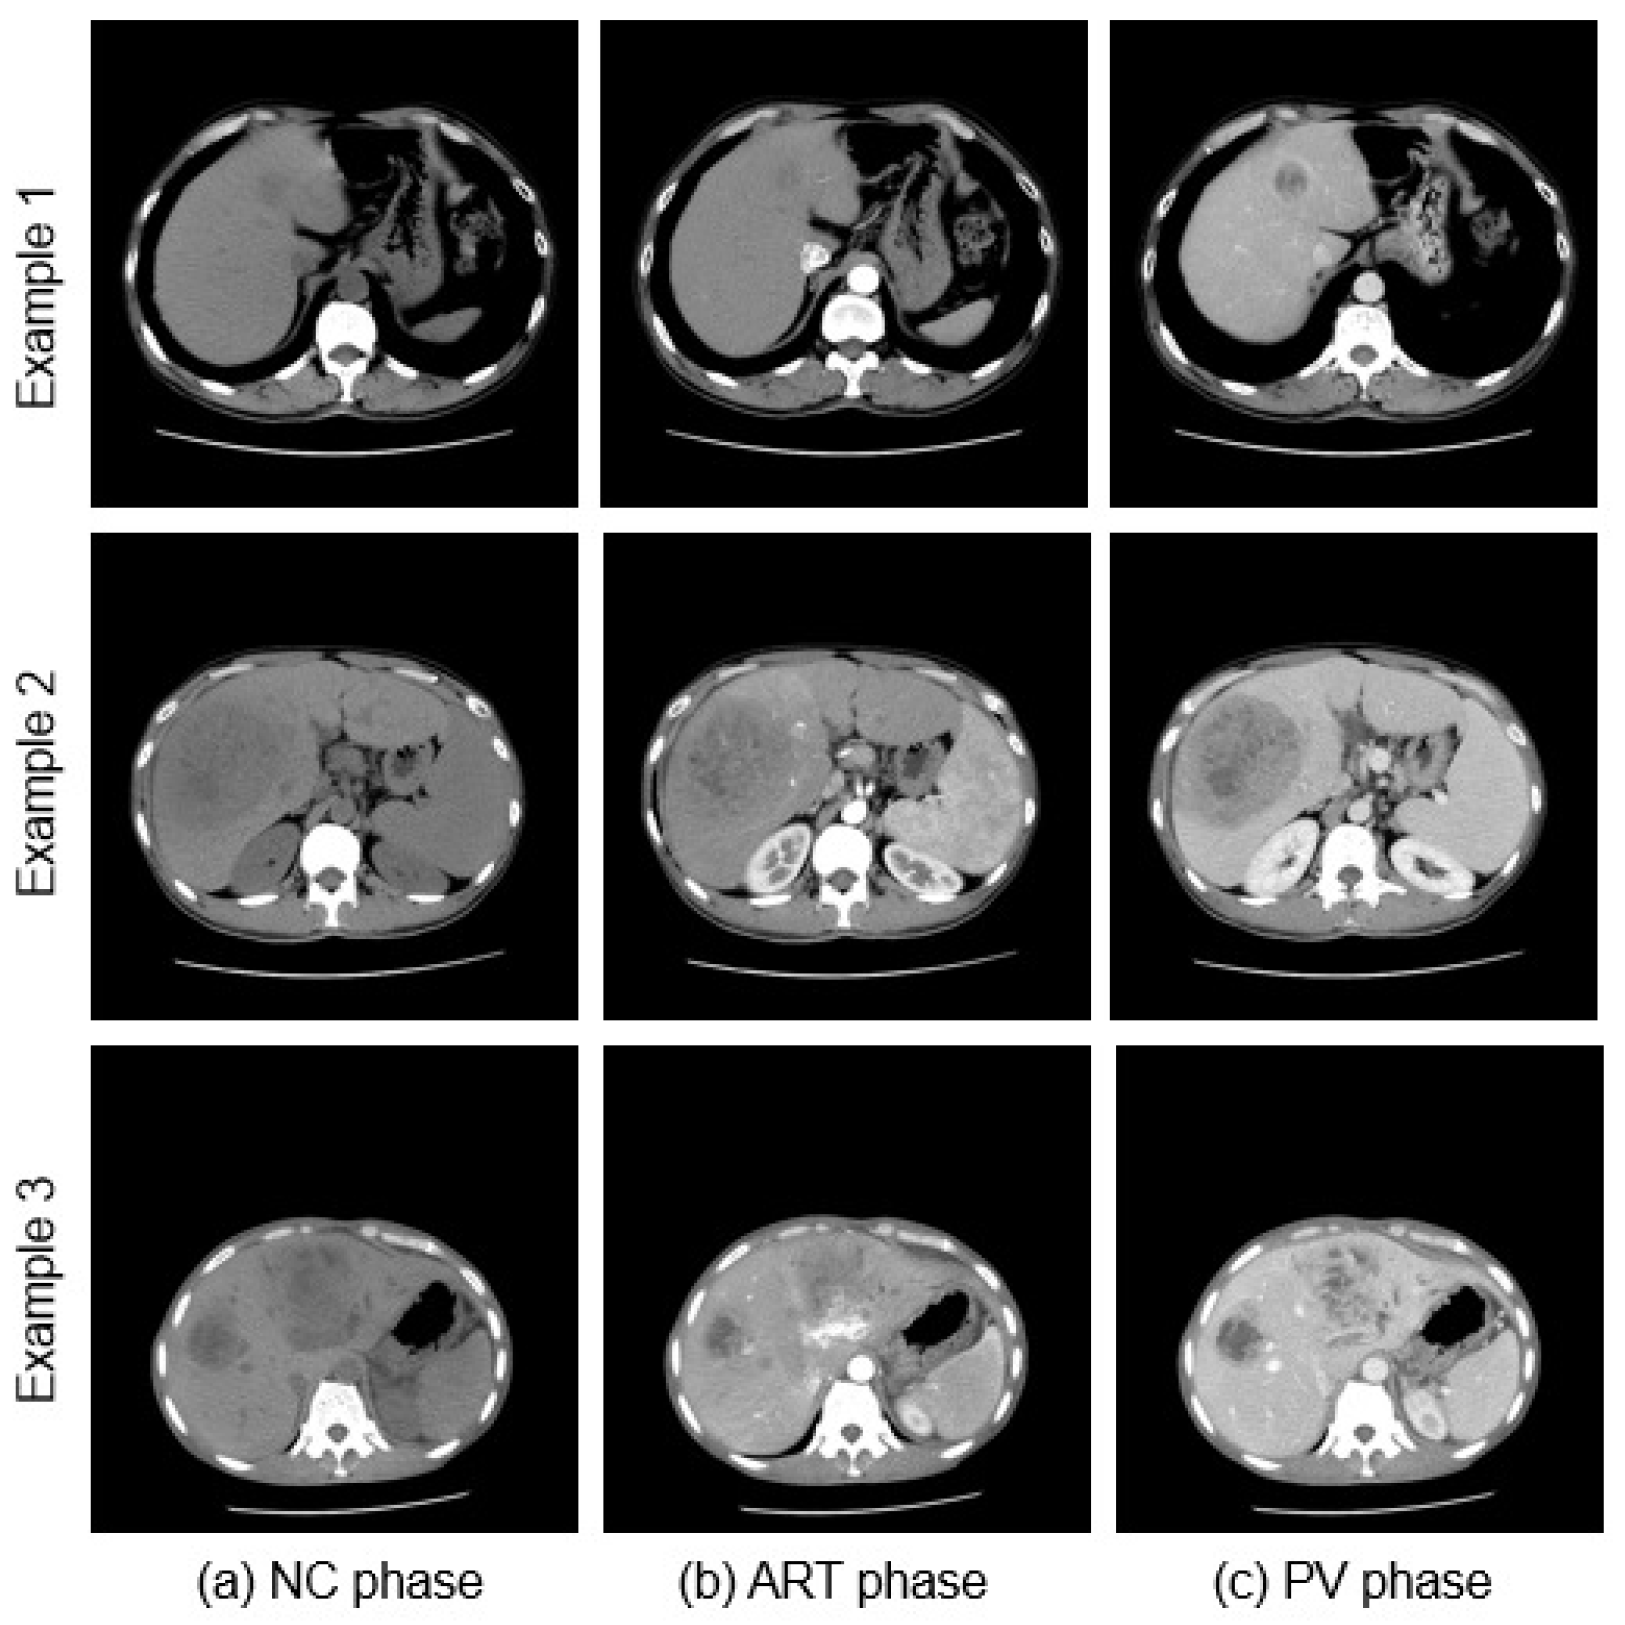

4.1. Dataset

4.2. Data Preprocessing